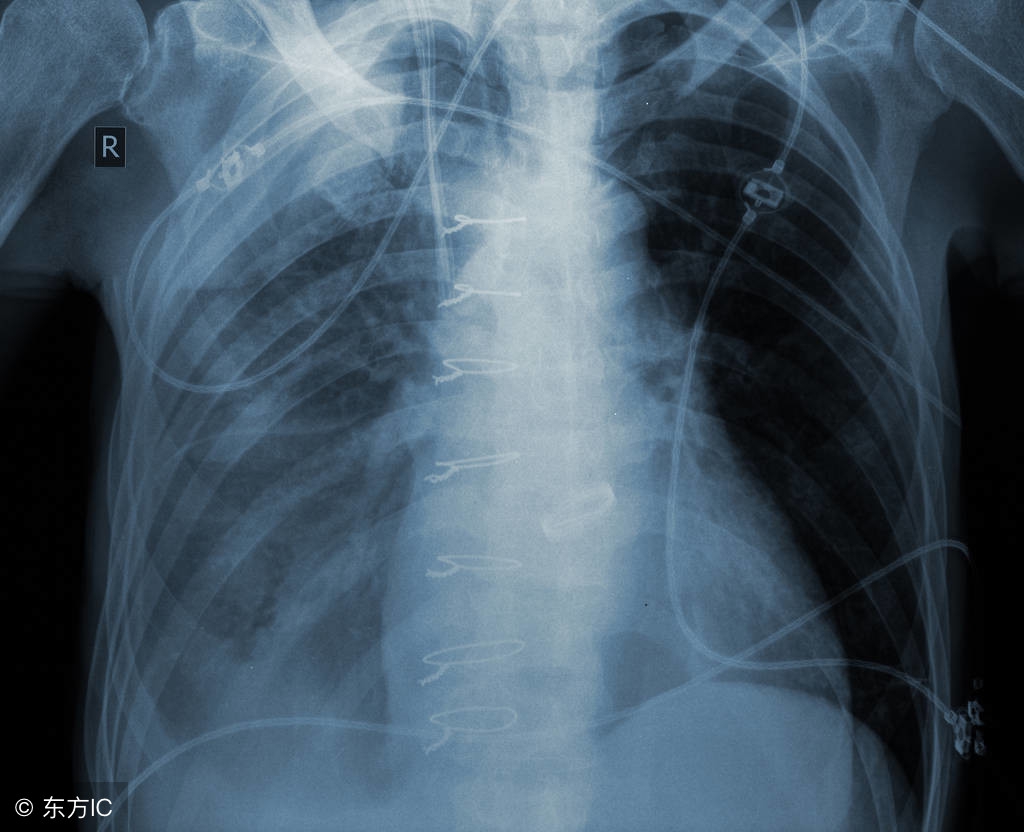

注:文中图片来自网络,如有侵权请联系删除